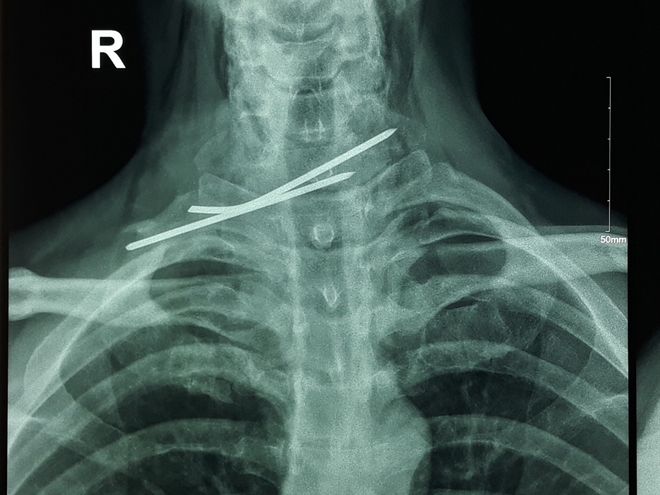

13/09/2018 21:28Người đàn ông bị đinh đâm xuyên thực quản, khí quản

Chiều 13-9, Bác sĩ chuyên khoa II (BSCKII) Nguyễn Minh Nghiêm, Trưởng phòng Kế hoạch - Tổng hợp Bệnh viện Đa khoa Trung ương (BVĐKTƯ) Cần Thơ cho biết, các BS của BV vừa cứu sống bệnh nhân nam 41 tuổi ở Sóc Trăng bị đinh kirschner kết hợp xương đòn đâm xuyên thực quản và khí quản.

Theo đó, bệnh nhân Nguyễn Văn P. từng được phẫu thuật kết hợp xương đòn phải do chấn thương cách đây 2 năm. Cách ngày nhập viện 10 ngày, bệnh nhân P nuốt đau, ho khạc ra máu. Đến ngày 5-9, thì bệnh nhân đến BVĐKTƯ Cần Thơ điều trị.

Qua thăm khám và làm các cận lâm sàng, như: X-quang ngực, CT-Scan, nội soi thực quản, bệnh nhân được chẩn đoán xác định dị vật vùng cổ do đinh kirschner kết hợp xương đòn đâm xuyên thực quản và khí quản.

Ê kíp phẫu thuật gồm Ths-BS Liêu Vĩnh Đạt, Ths Nguyễn Hữu Thuyết và BS Thương đã phẫu thuật lấy đinh và khâu lại thực quản, khí quản cho anh P. Hiện, sức khỏe bệnh nhân ổn định, đã ăn được, dự kiến xuất viện trong vài ngày tới.

Các BS khuyến cáo, bệnh nhân đã được phẫu thuật kết hợp xương bằng các dụng cụ (đinh, vít...) nên đi tái khám đúng theo sự hướng dẫn của thầy thuốc. Tránh trường hợp không tái khám hoặc tái khám quá muộn (như trường hợp này).

Các dụng cụ như đinh, vít nhỏ sẽ di chuyển nhiều nơi đâm xuyên các cơ quan gây nguy hiểm, nếu đâm xuyên các mạch máu lớn còn nguy hiểm tính mạng...